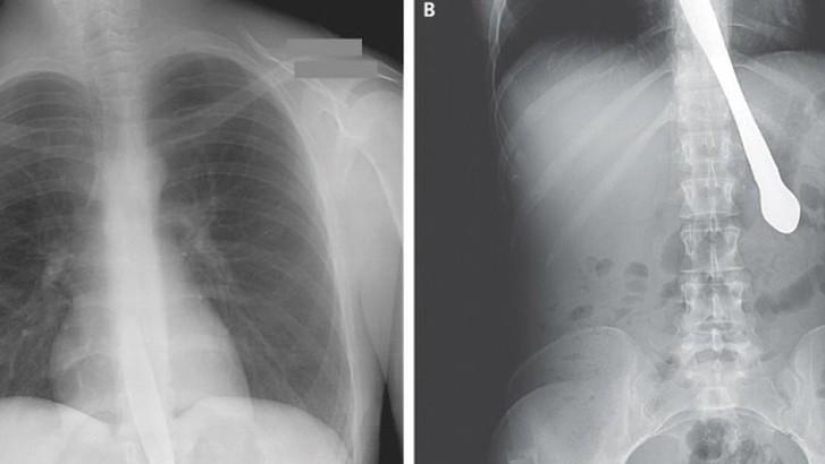

22. Pinzas quirúrgicas.

24. Tijera.